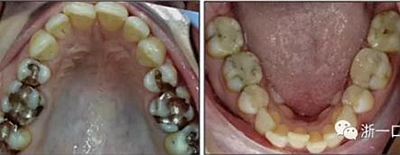

患者曾行正畸治療,現(xiàn)覺(jué)笑容不美觀前來(lái)就診。患者正面觀及側(cè)貌示下頜發(fā)育不足,偏高角,唇閉合不全。上下頜中線齊。覆合、覆蓋4毫米。磨牙關(guān)系及尖牙關(guān)系II類(lèi)。上頜擁擠度4mm,下頜擁擠度6mm。4顆第一前磨牙在第一次正畸治療時(shí)已拔除。上下牙弓呈尖圓型,牙弓狹窄。

由于下頜中切牙間沒(méi)有間隙行下頜正中切開(kāi)術(shù),故進(jìn)行術(shù)前正畸擴(kuò)展間隙。下頜前牙粘托槽,中切牙托槽成交放置,將中切牙牙根分開(kāi)。使用0.018X0.018鎳鈦絲及置于下頜左、右中切牙之間的推簧推間隙。3個(gè)月后拍攝CBCT示已有足夠間隙行下頜正中截骨術(shù)。

擴(kuò)弓保持8周后,除擴(kuò)弓器影響牙外粘接托槽,使用0.014鎳鈦絲進(jìn)行排齊、整平。旋轉(zhuǎn)停止后3個(gè)月拆除擴(kuò)弓器,全口粘接托槽,使用0.016niti繼續(xù)排齊整平。佩戴可摘保持器,保持上頜寬度。在使用至0.018x0.018niti7周,徹底排齊整平后,使用大弓型的0.016x0.022不銹鋼絲,繼續(xù)維持原有寬度,同時(shí)停止使用可摘保持器。掛II類(lèi)牽,糾正磨牙關(guān)系,使用鏈圈關(guān)閉散在間隙,少量使用IPR去除局部前牙的黑三角。術(shù)后9個(gè)月拍全景示,牙根平行度可,再無(wú)其他牙根出現(xiàn)問(wèn)題。1年7個(gè)月后治療結(jié)束。上下頜3-3舌側(cè)保持器+哈雷氏保持器進(jìn)行保持。